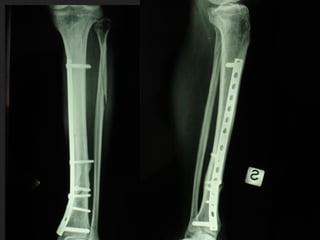

Dal Gennaio 2000 al Febbraio 2006 abbiamo trattato 167 fratture chiuse  con placca percutanea  in 164 pazienti :  27 lesioni diafisarie di gamba, 12 piloni tibiali ,  11 fratture prossimali di tibia, 36 fratture sovracondiloidee di femore, 17 fratture diafisarie di femore, 43 fratture metaepifisarie prossimali di omero, 21 diafisarie d’omero.  156 guarigioni 8 fallimenti

I buoni risultati ottenuti dipendono da 5 punti fondamentali:   una accurata riduzione percutanea della frattura  precise vie di accesso  l’utilizzo della placca che consenta il più lungo braccio di leva possibile il pretensionamento della placca  una sintesi con un ridotto numero di viti

Placche lunghe e pretensionate

Placche lunghe e pretensionate Sintesi con un ridotto numero di viti